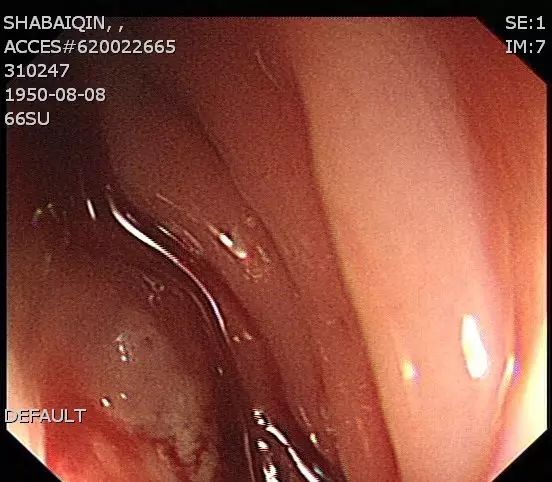

病例二:老年女性患者,来自吉林,一年前在当地医院因宫颈癌做了子宫及双侧附件切除术,近年7月份起因便血、腹泻伴体重减轻到吉林省人民医院查肠镜提示距肛门20cm一巨大肿瘤,病理为中分化管状腺癌。同时患者右下肢肿胀明显,血管超声提示有左下肢静脉血栓。